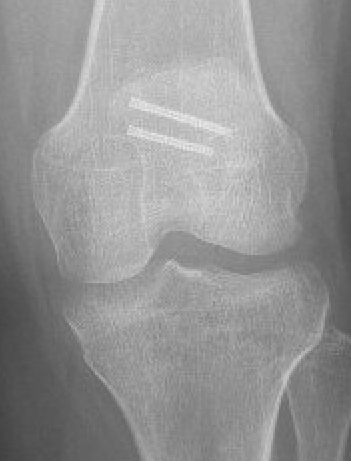

Open reduction and internal fixation

Fixation

Headless compression screws

Large osteochondral fracture medial facet patella